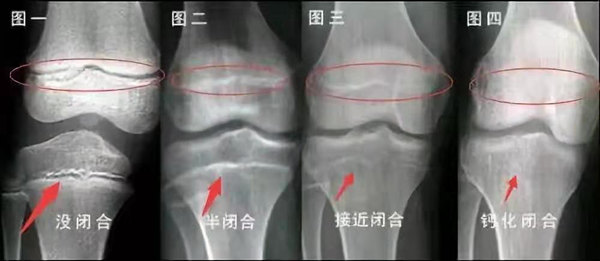

我們都知道,人體的高矮是由骨骼的生長發(fā)育決定的,特別是下肢長骨。長骨呈長管狀,在長骨的兩端有一種專管骨骼生長的骺軟骨,它與干骺端之間有一盤狀軟骨結(jié)構(gòu)稱為骺板(線),在幼兒的X光片上表現(xiàn)為一條較寬的透光帶。 (見下圖)

未成年時(shí)隨著年齡的增加骺軟骨端不斷骨化,骨骼就不斷增長。當(dāng)骨骺線完全閉合時(shí)骨骼就停止生長,個(gè)子也就不再增長了。一般骨骺端完全閉合的年齡是18~20歲左右。

骨骺線提前閉合最多見的情況是性早熟,而這也是很多醫(yī)生專家建議孩子進(jìn)行骨齡測量的原因之一。另外,在兒童時(shí)期大量補(bǔ)鈣也會(huì)使骨骺端提前過早閉合。

青少年一般什么時(shí)候骨骺閉合?

一般女孩是在16歲,男孩是在18歲。

一般來說,女孩的骨齡超過14歲,男孩的骨齡超過16歲,這時(shí)其骨骺線已接近閉合,基本沒有長高的機(jī)會(huì)了。

因此,越早了解骨骺線閉合情況,越早干預(yù),孩子長高的可能性越大。